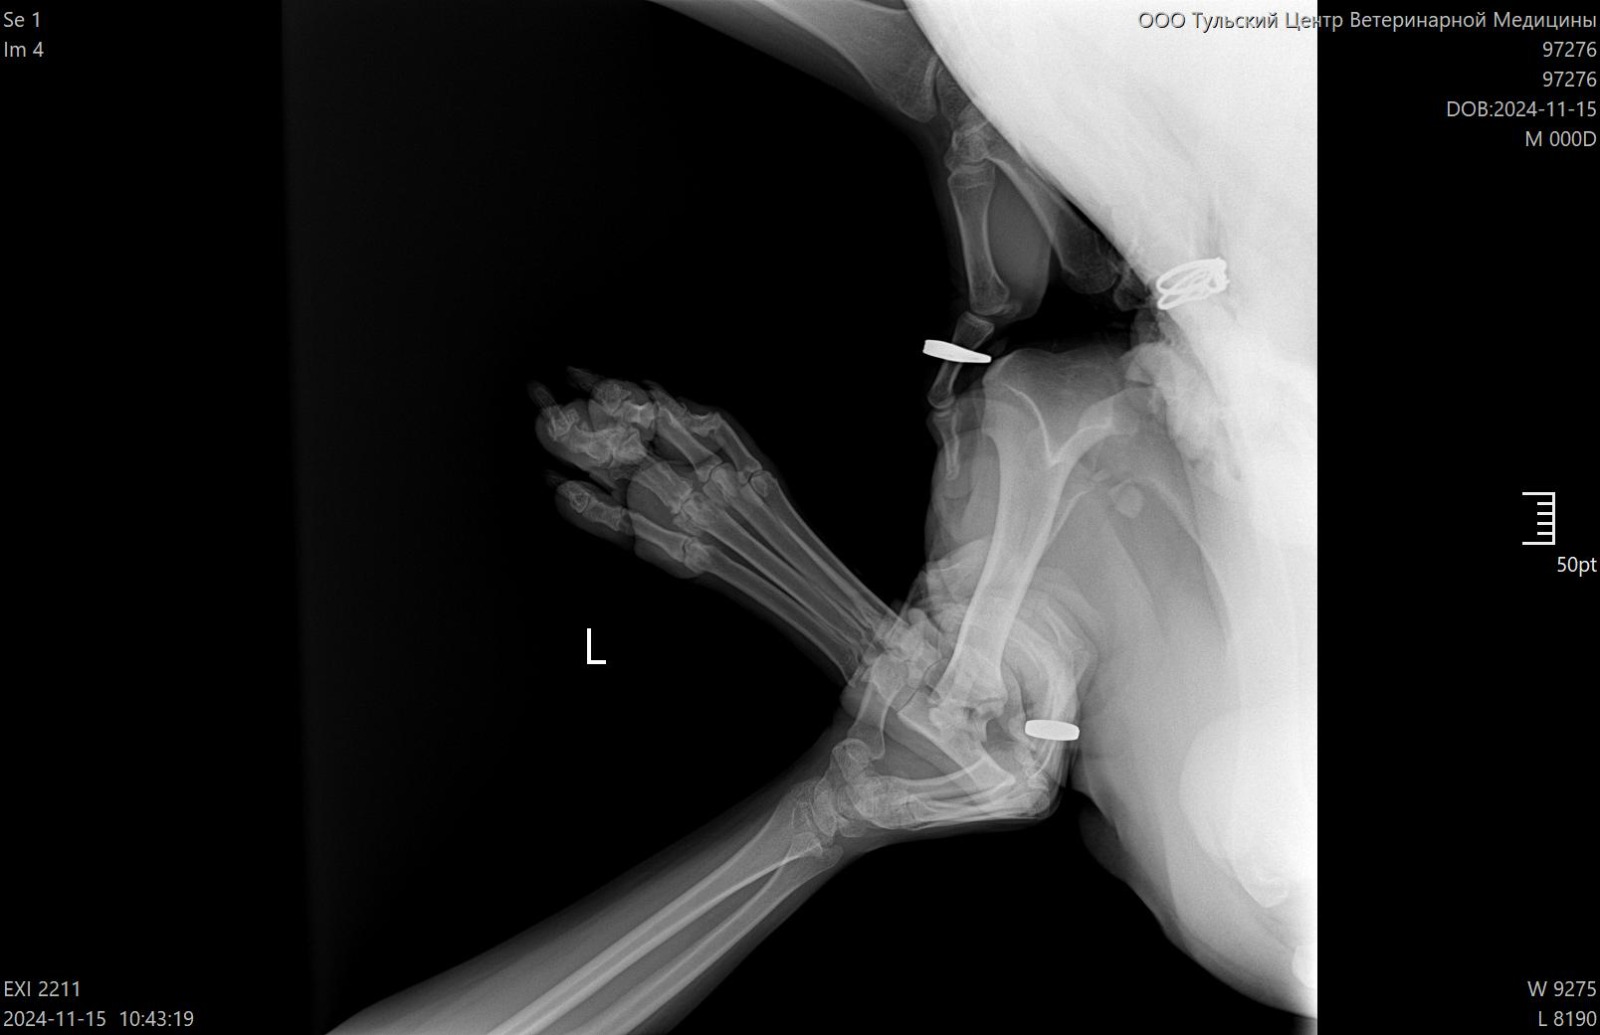

Рентген лапы, которая болит

Зона операции в снимок не попала....но со слов врача все нормально. То что видно - чисто....придется поверить, но так как шов подтекает, антиюиотик попробуем заменить на клиндомицин.

Сильнейший коксартроз тбс на больной лапе.....который не заметили на первичных осмотрах....зато настаивали в необходимости кастрации. В результате изменения положения лапы, нагрузки - воспаление и боль.